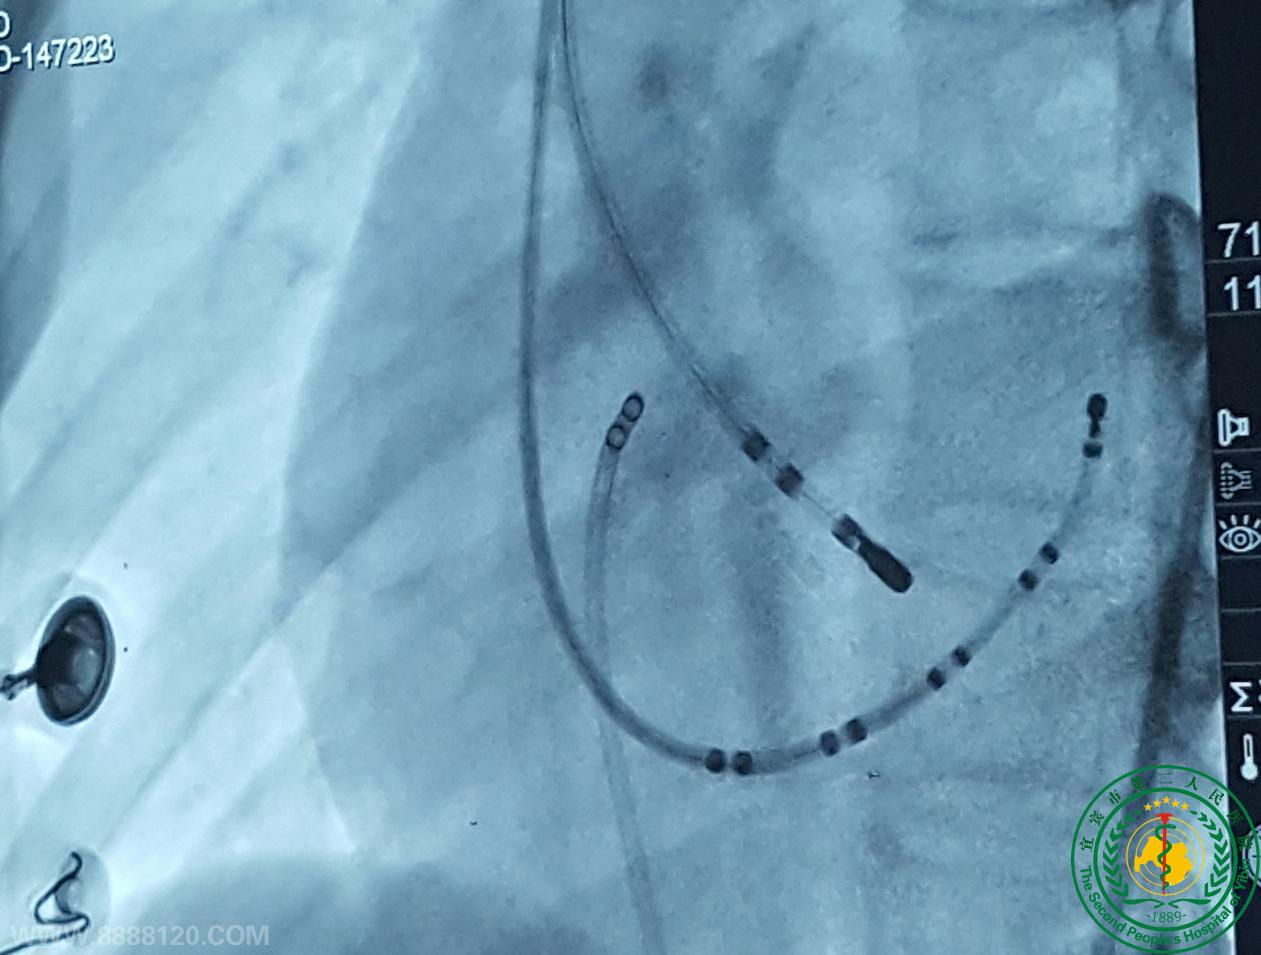

宜宾市第二人民医院 图文